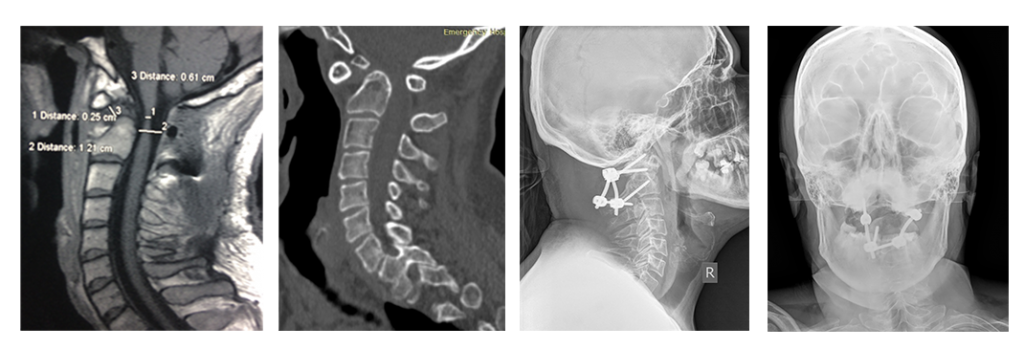

На рис.: схема минимальной фиксации атланта и аксиса с помощью 2-х пар титановых винтов (техника по Goel-Harms), соединенных титановыми стержнями. Схема установленных на позвонки направителей для винтов, изготовленных на 3Д принтере. Рентгенограммы ребенка 5 лет после проведения данной операции.

На снимках: ребенок 3 лет со спондилоэпиметафизарной дисплазией и тетрапрегией, имеется нестабильность в области краниоцервикального перехода с сдавлением спинного мозга. Стрелкой обозначен смещенный вперед атлант. Очень маленькие размеры позвонков. Проведена фиксация «второй шейный позвонок – затылок», костная пластика. Смещение атланта и нестабильность устранены. Восстановление движений в конечностях после операции. Ребенок самостоятельно начал ходить.

На снимках: пациент 36 лет с атланто-аксиальной нестабильностью и сдавлением спинного мозга на фоне врожденного порока развития «зубовидной кости» (обозначена стрелкой). Тетрапарез после незначительной травмы. Проведена передняя мобилизация для устранения смещения и задняя фиксация с устранением нестабильности, костная пластика.